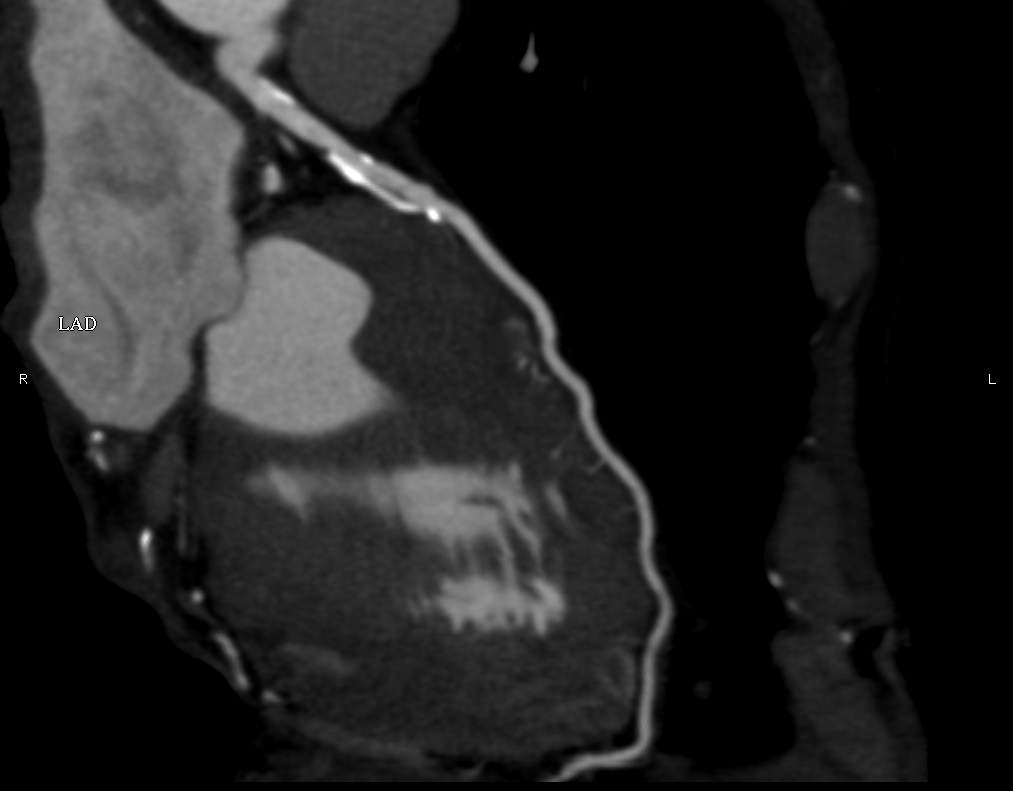

The conventional imaging modality of the coronary vessels is cardiac catheterization (coronarography) which is still an absolute indication in acute coronary syndrome. During the examination besides identification of the symptom causing stenosis or occlusion (culprit lesion), it is also possible to perform dilatation with a balloon catheter or stent implantation to restore flow. If either of these procedures is carried out within 6 hours of symptom onset, myocardial tissue dearth can be prevented or minimalized. Coronarography of patients with stable angina is only recommended if a high risk of coronary disease persists clinically. CT coronarography can replace cardiac catheterization in low and medium risk patient groups who present with angina-like chest pain. The examination has a very high sensitivity and negative predictive value for coronary disease; therefore, it is a sensitive screening tool for patients who present with chest pain as a symptom of coronary stenosis. It can also uncover alternative diagnoses for chest pain syndromes. CT examination is not only good in representing the vascular lumen, but it can also detect non-stenosing but vulnerable (lipid rich) plaques by showing a special morphologic appearance. These lesions might remain hidden during coronarography, producing false negative results with regard to an existing significant atherosclerotic involvement.

Fig. 3., 4., 5.: CT coronarography: Normal anatomy, volume rendered image and curved reformatted image Plaque causing stenosis on LAD coronary artery

Myocardial ischemia causes ventricular wall motion abnormalities, which in latent ischemia only appears with provocation tests. Ischemia induced cardiac hypokinesis and akinesis can be confidently detected with stress echocardiography or with MRI. Coronary stenosis related angina is caused by the decrease in myocardial perfusion. This can occur in resting state also but can be demonstrated more consistently with stress tests. Conventionally, perfusion evaluation is carried out with radionuclide examinations: either with 99mTc-sestamibi SPECT scan or with PET examination which can detect perfusion anomalies. MRI examination, carried out with complementary pharmacologically induced stress examination, can also prove to be highly sensitive with this regard.

If the diagnosis of coronary disease has already been proved, imaging is used to examine the viability of the myocardium. This is an important influencing factor, because revascularization techniques create a significant improvement in the ventricular function only if the recanalized myocardial territory shows viability in at least 50% of its wall thickness. Viability can be assessed with isotope examinations, CT or MRI. With MRI, on the delayed contrast enhanced images (5-10 minutes after iv. injection) the non-viable territories or scar tissue show characteristically increased enhancement; and they are easily distinguishable from viable myocardium. The wide-spread use of MRI in cardiac viability assessment is further justified by the fact that it does not necessitate the use of ionizing radiation. With only one diagnostic examination it still provides the best anatomic and functional analysis, demonstrates the functionality and the state of the myocardium and myocardial viability.

Fig.: 6., 7., 8.: MRI: Extended myocardial infarct of the inferior ventricular wall Late phase contrast enhancement in the thin inferior wall of the ventricle in cross sectional and longitudinal images, MRI